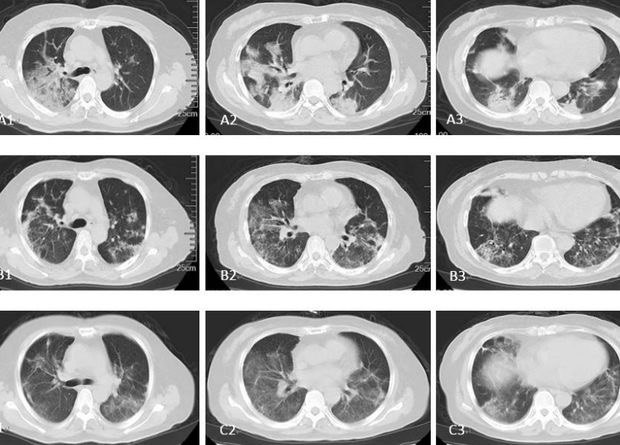

Против коронавируса все средства хороши. Две группы китайских врачей попробовали использовать в борьбе с ним стволовые клетки — и, кажется, преуспели. Правда, как всегда бывает в таких случаях, выборка крайне маленькая, статья еще не отрецензирована, а процедура довольно сложная и дорогая. Едва ли она когда-нибудь станет массовой, но, в любом случае, можно порадоваться за участников этих испытаний — все они быстро пошли на поправку